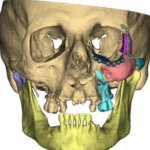

Our NJ team of Oral & Maxillofacial surgeons is trained to treat a variety of injuries to the mouth, face, and jaws. Our doctors maintain affiliations with NJ and NY hospitals and are often called to the emergency room to evaluate and treat traumatic facial injuries. Fractures (broken bones) can involve the lower jaw, upper jaw, cheekbones, eye socket, and combinations of these bones. Treatments for these injuries, such as jaw surgery are frequently managed in the operating room. Our doctors are board-certified and are on staff at Hackensack University Medical Center in NJ as well as Columbia University Medical Center in NY. We can manage and treat your injuries at any of these hospitals.